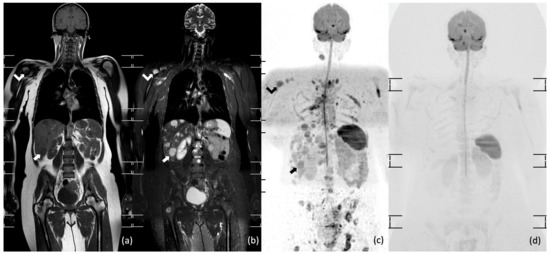

- Albano, D.; Patti, C.; Matranga, D.; Lagalla, R.; Midiri, M.; Galia, M. Whole-body diffusion-weighted MR and FDG-PET/CT in Hodgkin Lymphoma: Predictive role before treatment and early assessment after two courses of ABVD. Eur. J. Radiol. 2018, 103, 90–98. [Google Scholar] [CrossRef]

- Horger, M.; Claussen, C.; Kramer, U.; Fenchel, M.; Lichy, M.; Kaufmann, S. Very early indicators of response to systemic therapy in lymphoma patients based on alterations in water diffusivity—A preliminary experience in 20 patients undergoing whole-body diffusion-weighted imaging. Eur. J. Radiol. 2014, 83, 1655–1664. [Google Scholar] [CrossRef] [PubMed]